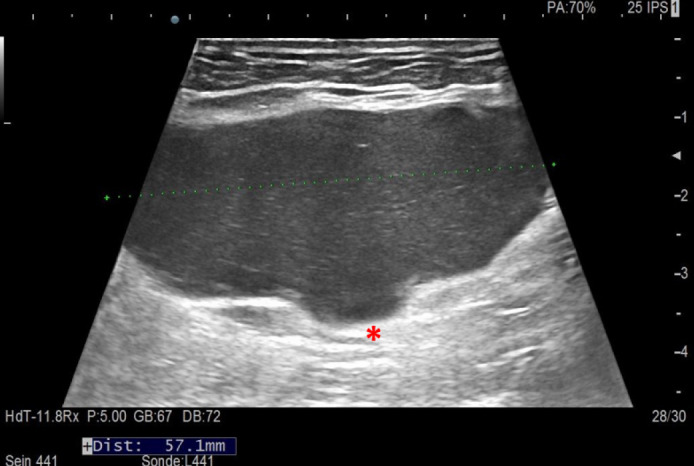

Tuberculosis (TB) of the rib is an uncommon manifestation of extrapulmonary TB that can pose significant diagnostic challenges, especially when presenting as a breast mass. We report the case of a 74-year-old woman who presented with a left breast lump, initially suspected to be a plasmacytoma due to its imaging characteristics and clinical history. The mass was surgically excised, and histopathological analysis revealed granulomatous inflammation with caseous necrosis, suggesting TB. TB-polymerase chain reaction confirmed the diagnosis, despite negative Ziehl-Neelsen staining. The patient was treated with anti-tubercular therapy for twelve months, resulting in a favorable clinical outcome. This case highlights the importance of considering rib TB in the differential diagnosis of breast masses, particularly in endemic areas, and underscores the role of comprehensive diagnostic evaluations for timely and effective treatment.